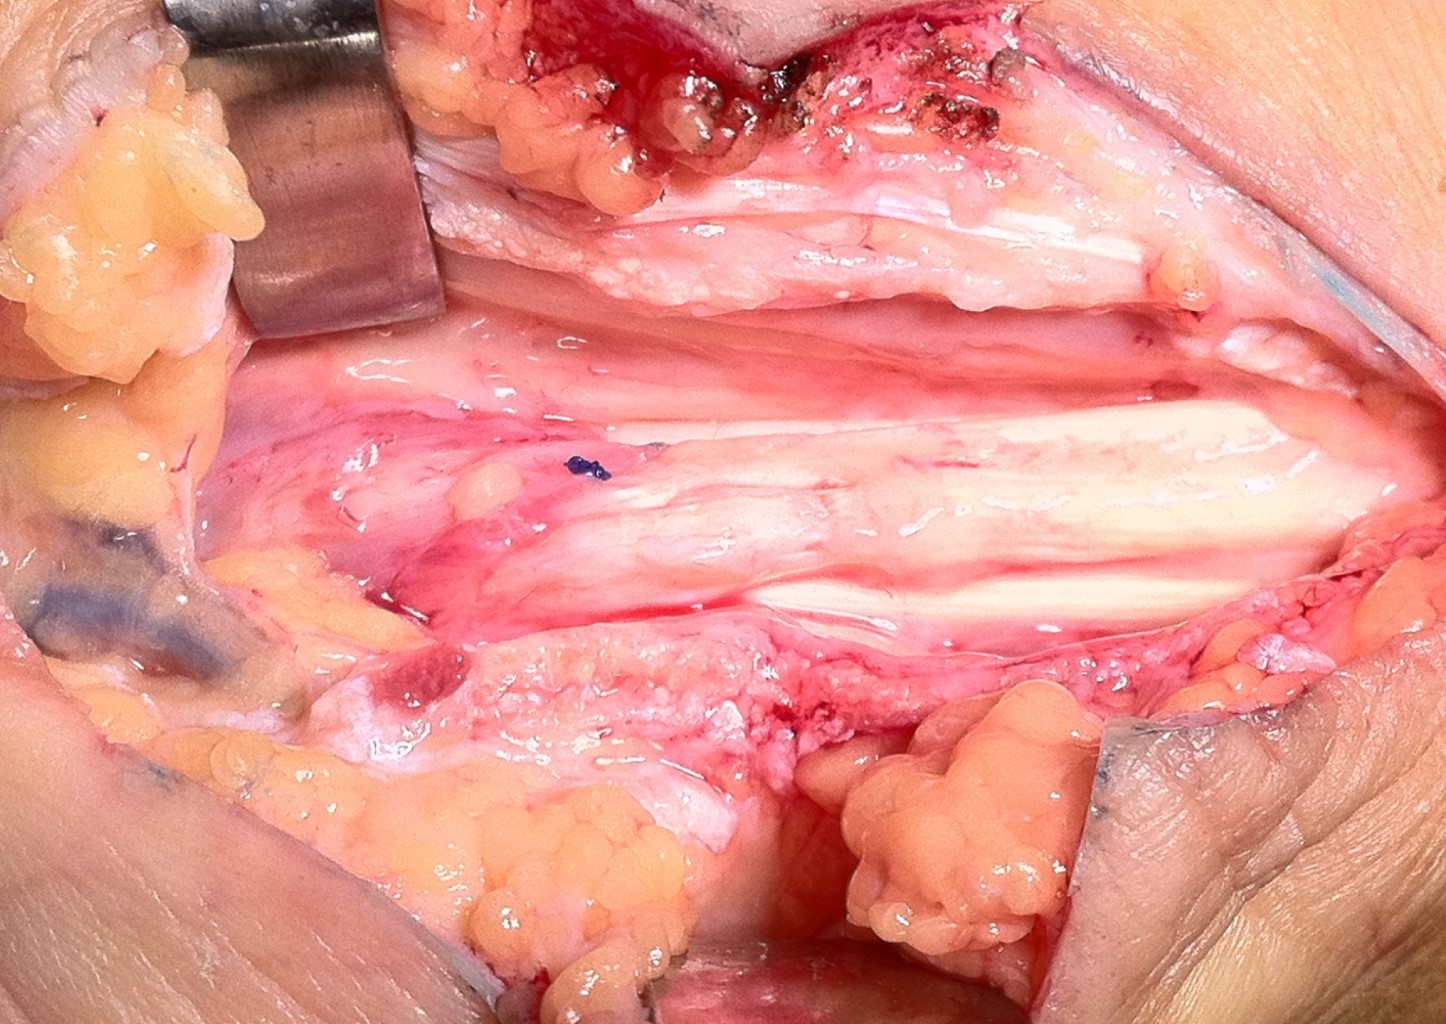

Se reingresó a la paciente (26/10/10) con alteración en la velocidad de sedimentación globular (VSG) de 32 mm/h y con el resto de estudios preoperatorios dentro de parámetros normales. En Octubre de 2010 se le realizó una exploración quirúrgica de la mano y muñeca con un abordaje palmar de 10 cm, que inició desde la incisión previa para el túnel del carpo, continuó paralelo al pliegue palmar, cruzó de forma oblicua los pliegues cutáneos de la mano y se prolongó hasta 3 cm distales al pliegue cutáneo proximal. Encontramos que tanto la polea como el ligamento transverso carpal estaban adecuadamente liberados. Sobresalió la presencia de una tumoración ovoide encapsulada, que midió 3.0 × 2.0 × 1.0 cm con superficie externa lisa, blanquecina, de consistencia blanda "ahulada", fija a la vaina tendinosa del flexor común superficial de los dedos, hasta el músculo lumbrical del tercer dedo. Se realizó estudio histopatológico (08/11/10), que reportó tejido fibroso y un fibrolipoma encapsulado (Figuras 1, 2 y 3).

Actualmente la paciente se encuentra asintomática, con cicatriz en la cara palmar de la muñeca derecha de 10 cm, normotrófica, sin dolor o parestesias ni sensación de chasquido, sólo con debilidad (4/5 de Daniels) a la flexión de los dedos de la mano derecha (Figuras 3 y 4).